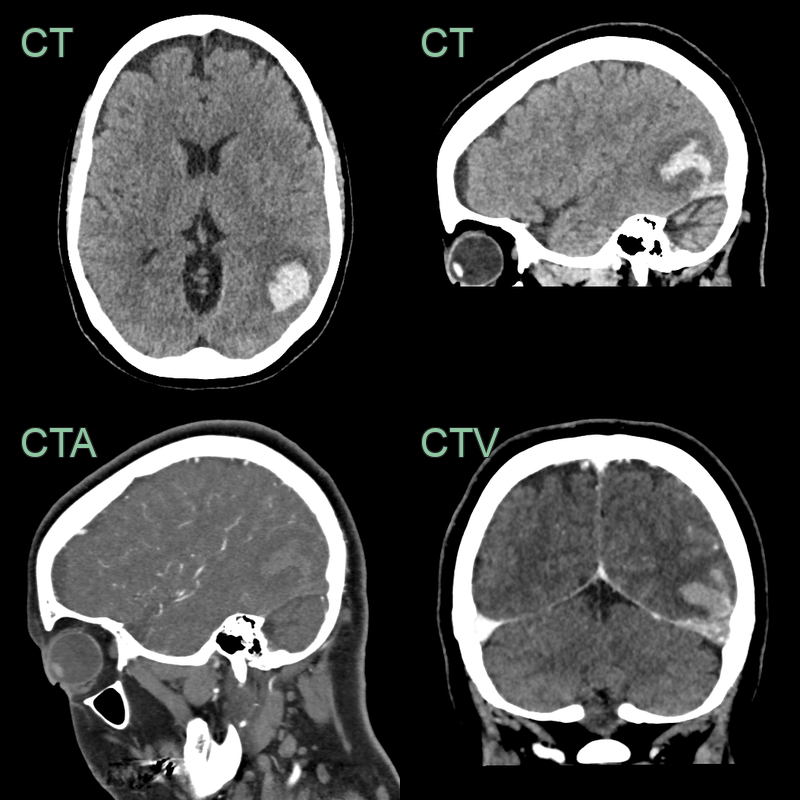

- 50-year-old patient presented with headache and dysphasia.

- CT showed a hyperdense superior sagittal sinus and a lobulated, fractionated, haematoma in the left parietal and occipital lobe.

- Despite a successful venous thrombectomy, thrombus reaccumulated in the superior sagittal sinus and the haematoma enlarged.